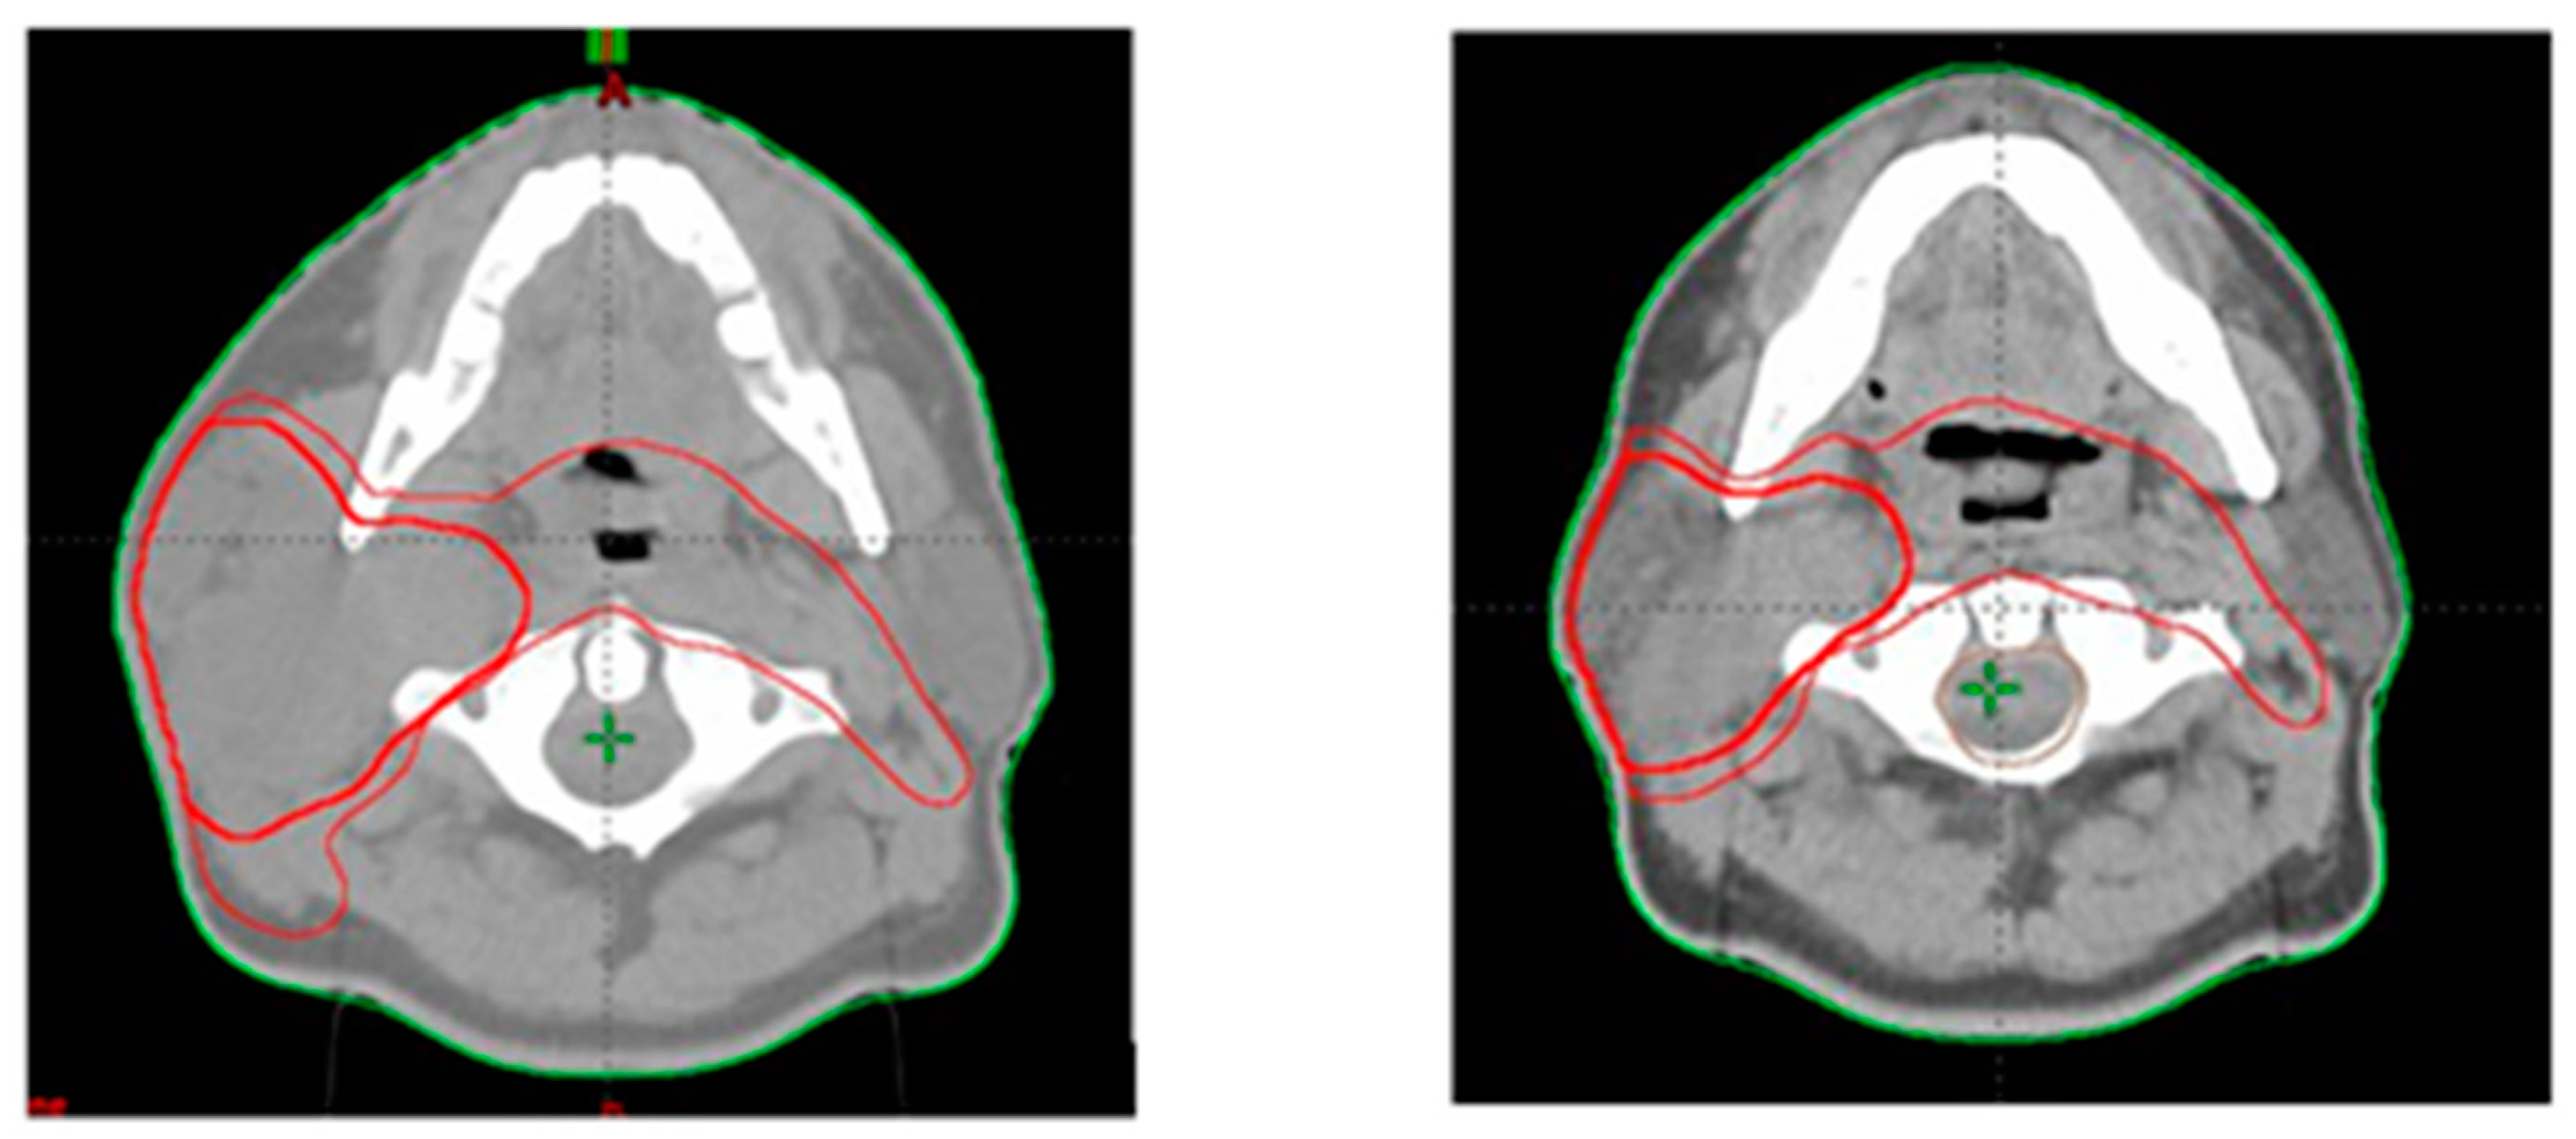

2.2. Target Volume Delineation

3.1. PTV Shrinkage

3.2. Parotid Glands Shrinkage